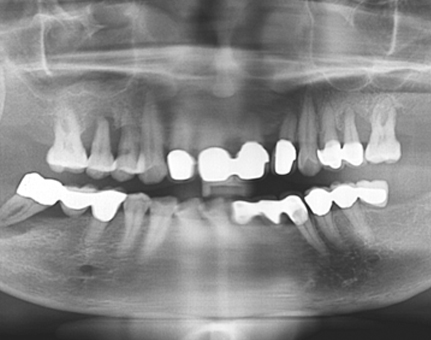

문치과 임플란트 사례

모든 전후 사진은 단순한 비교가 아닌,

환자분의 고민과 변화의 기록입니다.

문치과는 각자의 사연에 맞는 해답을 찾습니다.